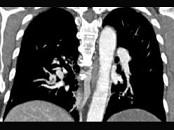

问题 男,56岁,食管癌术后,胸痛,呼吸困难,结合CT图像,最可能的诊断是 ( )

选项 A、肺水肿 B、肺不张 C、肺栓塞 D、支气管扩张 E、食管癌肺转移

答案 C